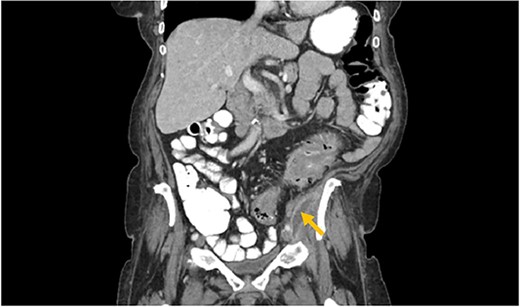

The patient had leukocytosis of 18.23 (Normal: 3.4–11 k/cmm) and CT scan of the abdomen pelvis without Intravenous contrast showed sigmoid diverticulitis with partial resolution of psoas abscess. However, it revealed a tract from the abscess to the hip (Image 3). After a prolonged discussion with the patient, she agreed to proceed with surgical intervention. She underwent exploratory laparotomy. There was a firm, inflamed sigmoid colon densely adherent to the psoas muscle. She also had two loops of small bowel that were densely adhered to the colon. Those loops were removed in block and two small bowel anastomoses were created. After mobilization of the sigmoid colon, there was a defect with fistulization to the psoas muscle. There was a significant amount of purulent fluid coming out of the psoas muscle, which was copiously suctioned and irrigated. Then, an end colostomy was created. A 3 cm elliptical incision was made in the left thigh and the skin was removed. The tissue was probed digitally, and we were able to identify the tract with a significant amount of stool and purulent fluid emanating from the left thigh. Once the cavity was entered, pressure was applied on the thigh, the psoas abscess was draining as well, indicating communication. We drained as much as we possibly could through both the psoas and the left thigh abscess and irrigated them copiously and packed. The patient was hemodynamically stable during the procedure and was extubated and transferred to the floor. The nasogastric tube was removed on post operative day 2, and she started on a diet. Her left hip dressing was changed daily with no signs of further infection. She continued on antibiotics during all hospital stay. She was discharged to Nursing home for physical therapy and adequate wound care. Specimen pathology was negative for malignancy. Patient was successfully reversed 6 months later.

Arrows shows extension of psoas abscess through abdominal wall in the surrounding tissues around the hip. There is not Hip bone involvement. Circle shows abscess next to the hip.